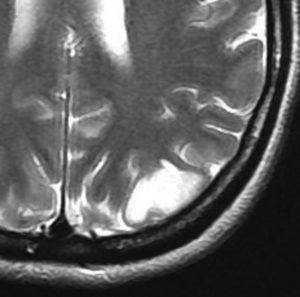

T2-FLAIR mismatch sign (T2とフレアの信号が違うこと)

protoplasmic astrocytomaに特徴的なMRI所見です。T2強調画像(左側)では白く(強い均一な高信号)見えます。でもフレア画像(右側)では白く縁取ったように見えます。びまん性星細胞腫の大きな特徴とされます。内部がとても柔らかいドロドロした腫瘍のこともあります。